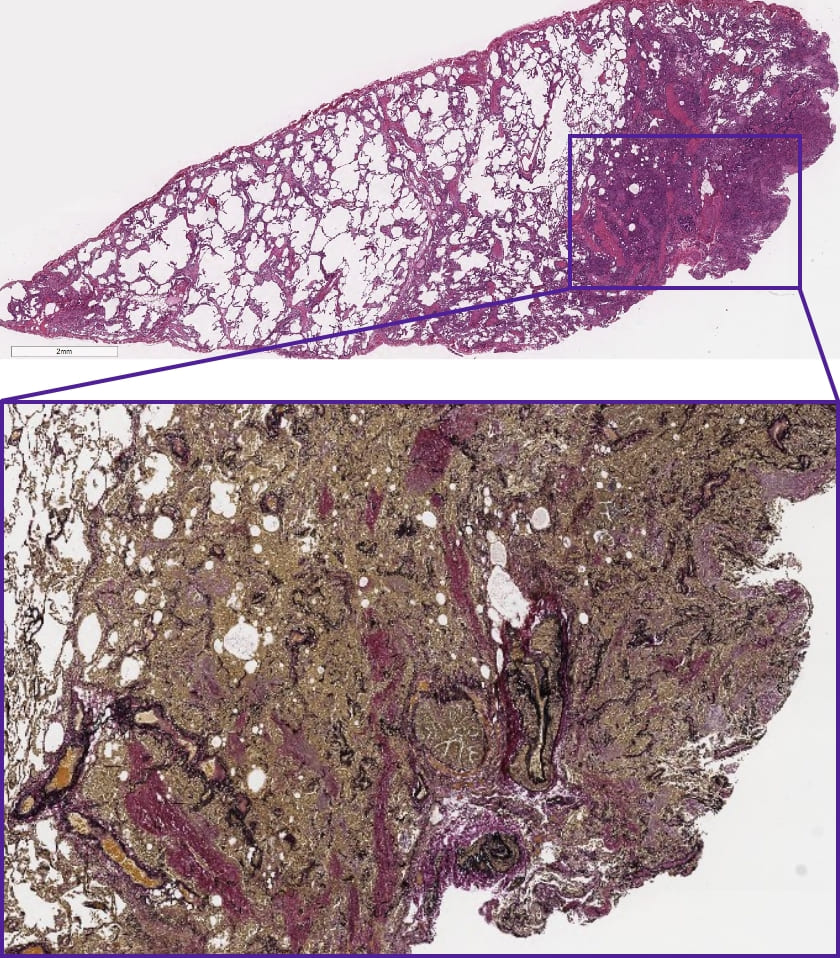

この症例の外科生検検体は?

DATA 1| X 線検査結果